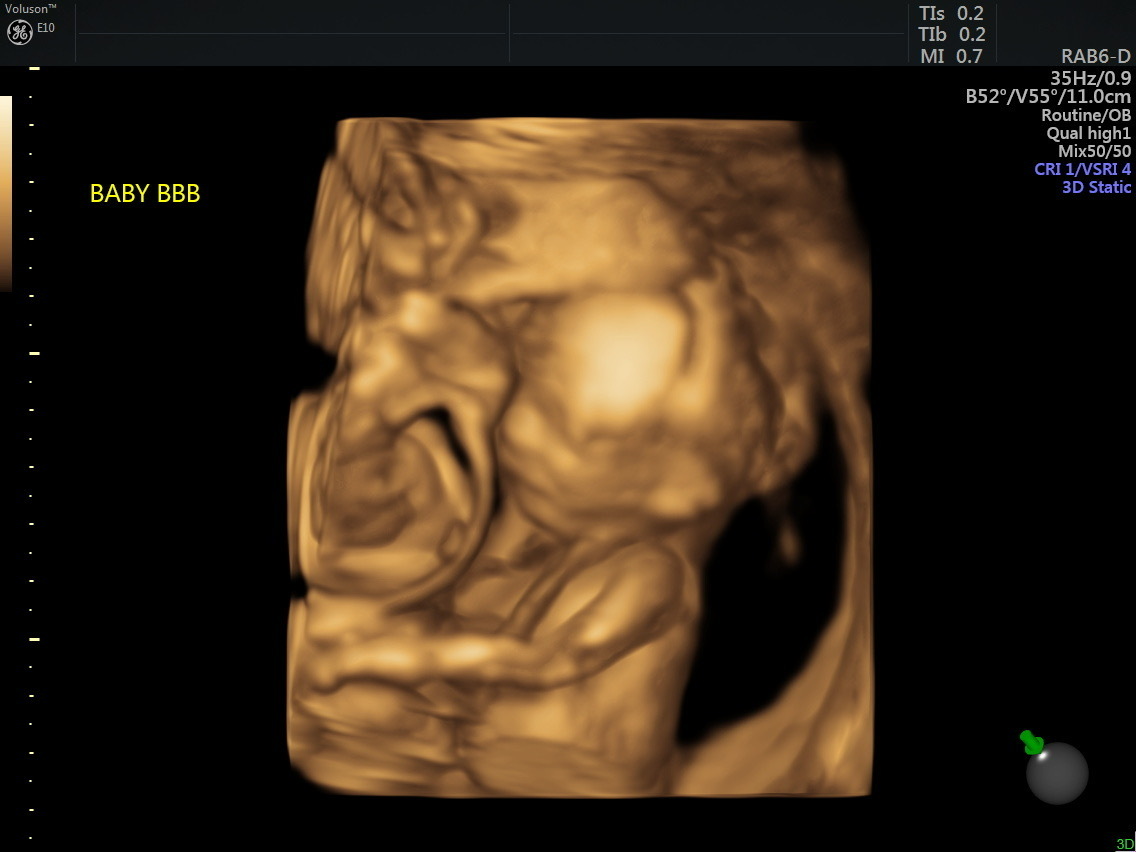

Bowen had been part of a social media group for those seeking to adopt out embryos. She said it was there that one post caught her eye. Both embryos had preimplantation genetic screening, or PGS. It had a one percent chance of successful implantation. Bowen and her husband chose to implant two of this woman’s embryos.

“I prayed they would both survive and that we would have fraternal twins,” she said.

The first trimester went very well, she said. However, at 15 weeks, Bowen’s water broke. “They told us Baby A lost his entire amniotic sac and his survival likelihood was very low.”

At 22 weeks Bowen began to lose more fluid. She was hospitalized and the babies were delivered at 24 weeks via emergency C-section this past January 2023.

Baby A, named Jeremiah, was born with a prolapsed umbilical cord. Before his birth, doctors were not certain he would have lungs. However, the baby boy was born with both lungs in place. He was intubated and placed in an isolette.

Jeremiah was born weighing one pound, six ounces. Twin Jonathan weighed one pound, 13 ounces. Jonathan was able to come home to the Bowen household in June. Jeremiah’s journey has been the most difficult.